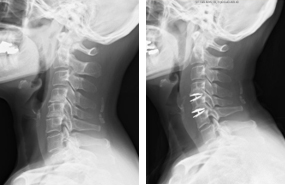

頚椎椎弓形成術の代表的な手術法に、片開き式脊柱管拡大術があります。ご高齢の方に対しても、安全で安定した成績が報告されている優れた術式です。手術は首の後ろを切開して、椎弓の両側に骨の溝を掘り、扉を開くように脊柱管を拡大します。開いた椎弓は再度閉じないように糸で固定したり、金属性のプレートで固定します。通常、手術翌日より座位や歩行訓練を行います。手術後のカラーは、病態により装着を考慮します。

(左)術前のMRIでは、全体的に脊柱管内の狭窄があります。(中)片開き式脊柱管拡大術を施行し、金属性のプレートで椎弓を固定しています。(右)手術により脊柱管が拡大され、神経症状が改善しています。